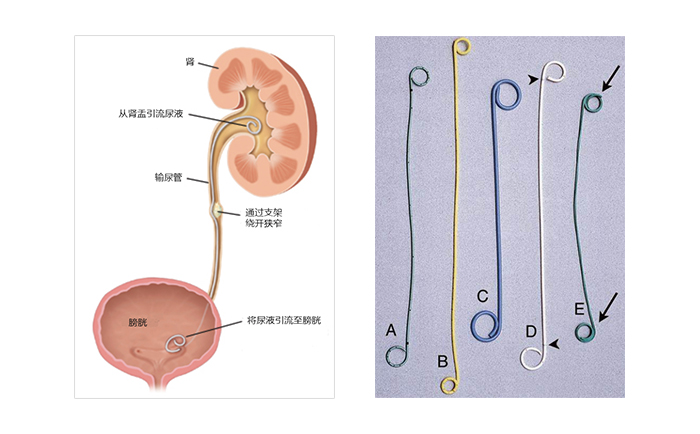

雙J管的作用

對于輸尿管狹窄的治療策略有很多,包括開放手術,經腹腔鏡輸尿管切除術,腎造口術等。其主要目標都是創建新的通道,讓尿液能順利排出腎臟。雙J管(double-J tube)又稱D-J管,是常見的輸尿管支架,兩端呈豬尾型彎曲,置于輸尿管內,既可以起到尿液引流作用,又可防止其滑入腎臟或膀胱。雙J管置入作為一種微創治療方式,是實現輸尿管疏通最常見的一種選擇,相比其他治療策略,手術時間更短,對患者的創傷也更小。

來自網絡:輸尿管支架工作原理及常見的雙J管